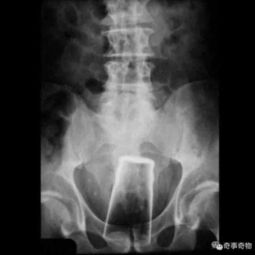

据Dailymail报道,一名24岁的男子做出了令人大跌眼镜的举动,上周六深夜,该男子因身体极度不适被紧急送往朗格伊医院急诊科,起初,男子只是含糊承认自己往直肠里塞了个大物件,死活不肯透露具体是什么,医生在手术过程中取出物体时,惊恐地发现这竟是一枚1918年生产的德军37毫米口径炮弹,长度约20厘米。

由于无法判断这枚炮弹是否还具有爆炸威力,医院立刻拉响了警报,启动应急预案,消防队迅速赶到现场严阵以待,防爆专家也被火速召集到手术室进行专业评估,急诊科周边迅速拉起了安全警戒线,部分病区的员工和患者被紧急疏散,整个医院陷入了一片慌乱之中。

幸运女神在关键时刻伸出了援手,经过防爆专家的仔细检查,这枚由黄铜和铜制成的炮弹已经失去了活性,不会发生爆炸,这一结果让所有人悬着的心终于落了地,原本紧绷的神经也得以放松。